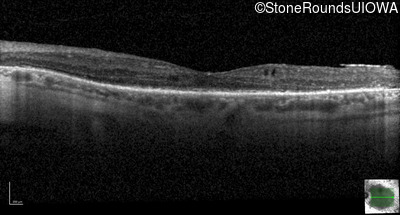

Age at visit: 46 years

This 46 year old man has had poor vision in dim light since age 2.

Diagnosis & molecular findings

AR Retinitis Pigmentosa SLC24A1 Met252 del2ggaAT Leu1052 del2ctTC AR